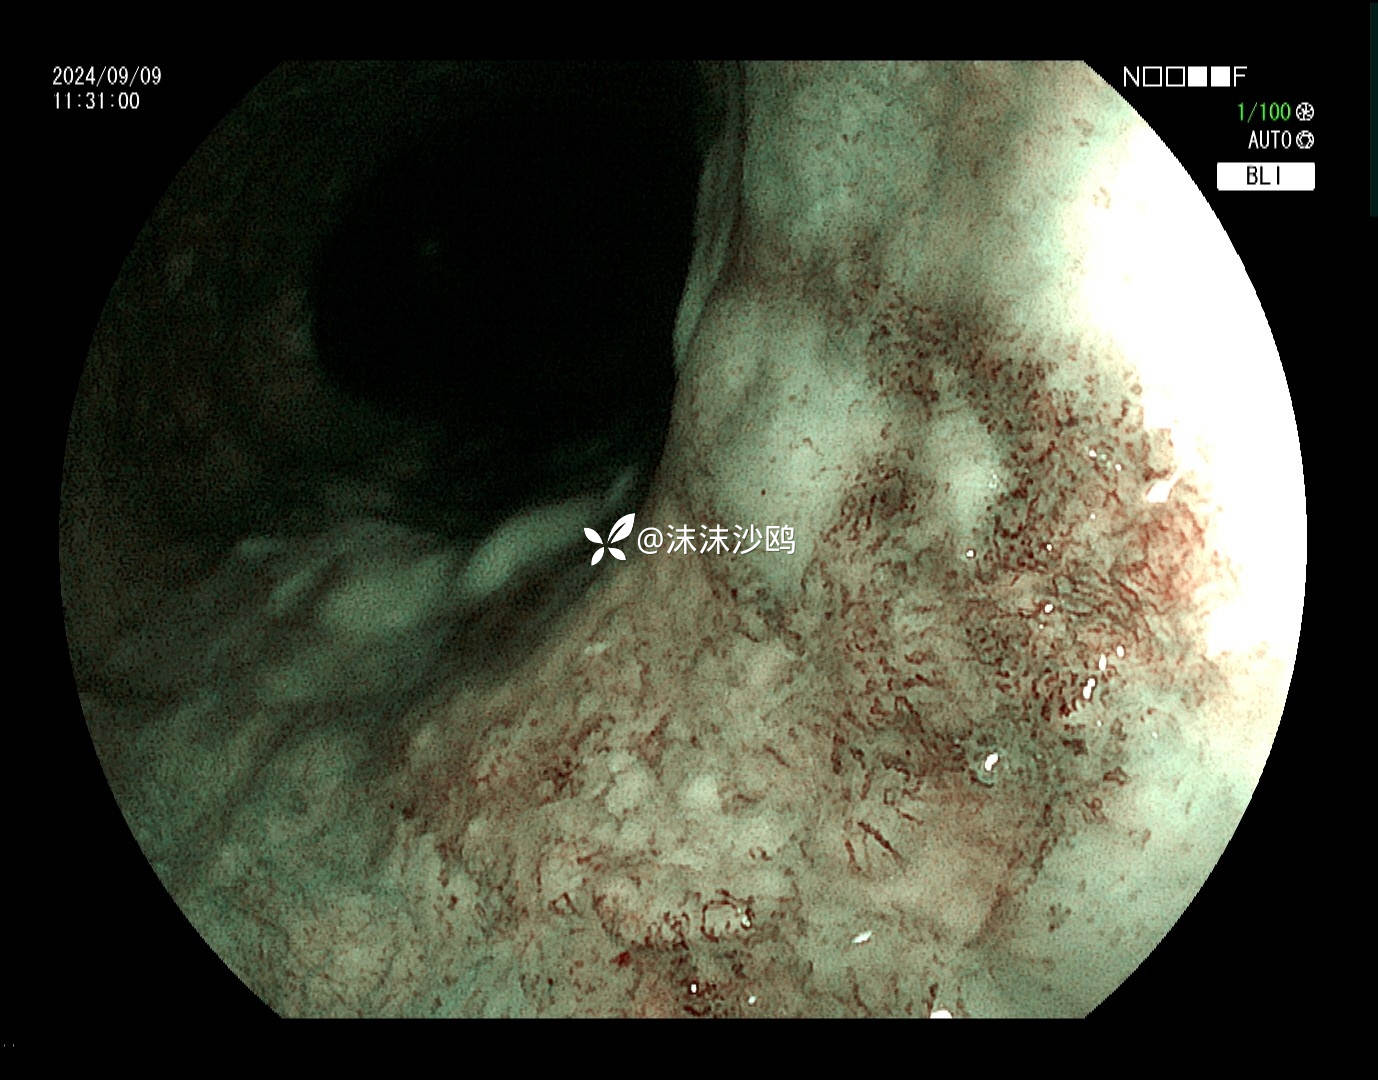

病灶肛侧

该患者平素无明显症状,吸气注气观察病灶延展性,柔软度可,白光观察粘膜呈现发红粗糙,BLI放大观察呈现明显茶褐色,可见B1型血管,局灶可见紊乱生长的B2型血管,并见AVA区域,感觉小于0.5mm。镜下考虑浸润深度,不超过SM1,应该有内镜下D的可能性。等病理结果,希望符合内镜诊断。